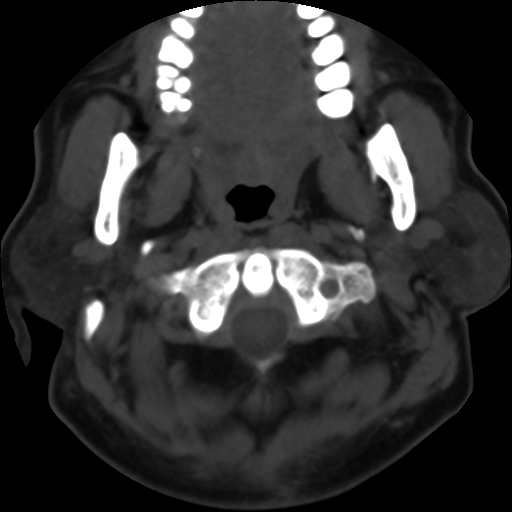

平扫: